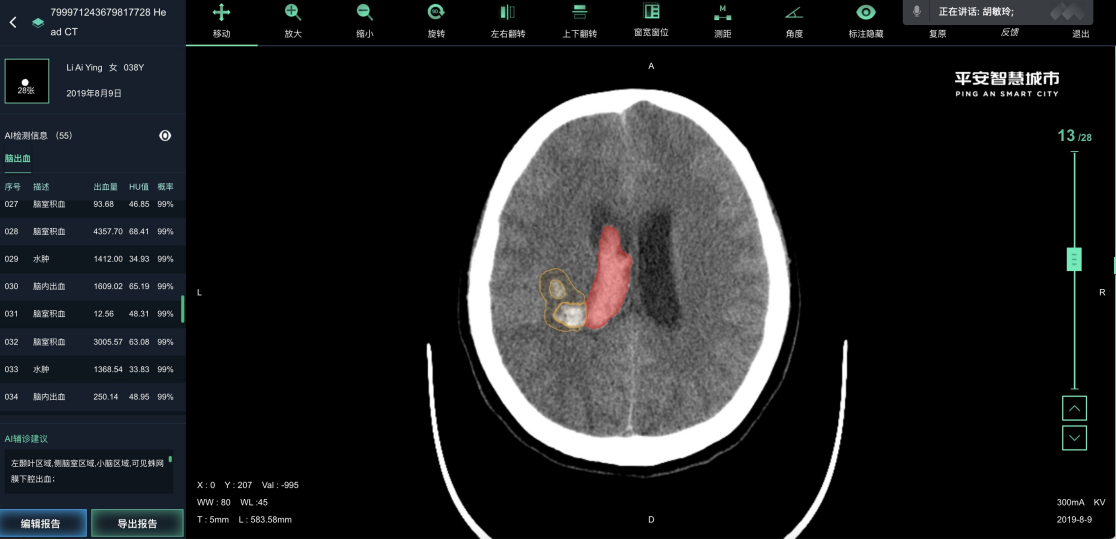

白云医疗影像系统是广州市白云区卫健委推动健全社区-中心医院体系的中间平台。白云医疗影像系统联合中心平台和各个社区医院实现患者影像检查的诊断和会诊功能。从中心平台可得到各个社区医院上传的患者影像数据进行诊断和联合会诊,并将诊断报告返回给中心平台。通过点击患者影像检查单中的AI影像分析按钮,可以跳转至AI影像分析系统上查看该患者的AI影像分析结果。普通影像分析和AI影像分析的结果可以大大地提高医生对患者病情诊断的准确率和效率,加强了各级社区医院与中心医院主治医生的交流与合作,均衡了各级医院医生资源,为广大患者带来更多便利。

为医疗影像提供了一种针对docom格式的图片文件的标注工具和存在方式。为不同医院的医生搭建远程会诊桥梁,实现AI阅片。